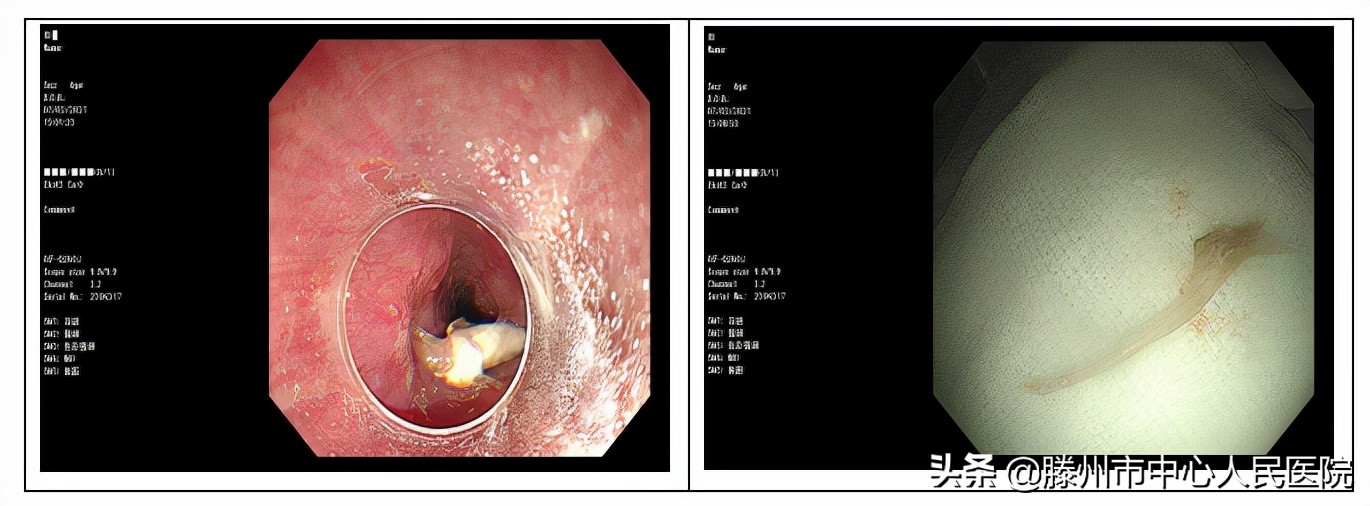

鱼刺